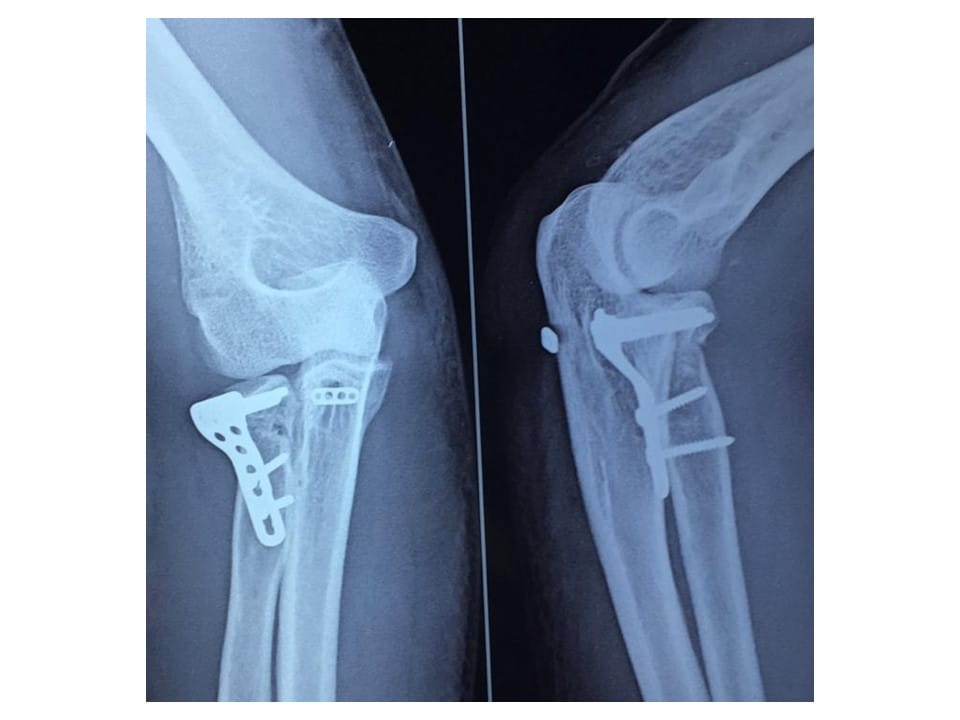

Terrible Triad